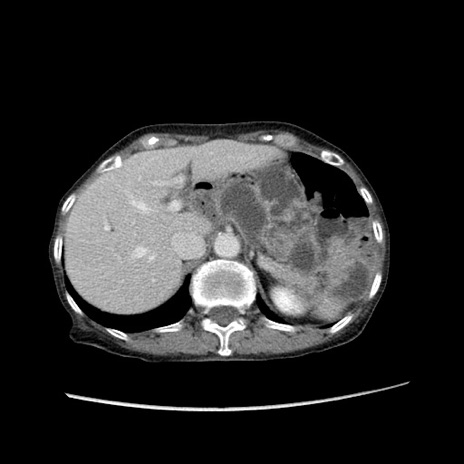

症例25(横断像)

【症例】80歳代女性

【主訴】胸のつかえ感

【現病歴】約9時間前に食後から胸のつかえた感じあり、嘔吐あり、来院。

【既往歴】胃癌(全摘)、胆摘、虫垂炎

【身体所見】心窩部に圧痛あり、反跳痛なし。

【データ】WBC 5700、CRP 0.05